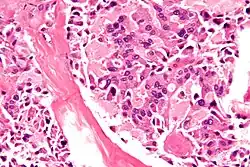

Micrograph of medullary thyroid carcinoma, as may be seen in MEN 2b. H&E stain.

Multiple endocrine neoplasia type 2B (MEN 2B) is a genetic disease that causes multiple tumors on the mouth, eyes, and endocrine glands. It is the most severe type of multiple endocrine neoplasia,[2] differentiated by the presence of benign oral and submucosal tumors in addition to endocrine malignancies. It was first described by Wagenmann in 1922,[3] and was first recognized as a syndrome in 1965–1966 by E.D. Williams and D.J. Pollock.[4][5] It is caused by the pathogenic variant p.Met918Thr in the RET gene. This variant can cause medullary thyroid cancer and pheochromocytoma. Presentation can include a Marfanoid body, enlarged lips, and ganglioneuromas.

MEN 2B typically manifests before a child is 10 years old. Affected individuals tend to be tall and lanky, with an elongated face and protruding, blubbery lips. Benign tumors (neoplasms) develop in the mouth, eyes, and submucosa of almost all organs in the first decade of life.[6] Medullary thyroid cancer almost always occurs, sometimes in infancy. It is often aggressive. Cancer of the adrenal glands (pheochromocytoma) occurs in 50% of cases.